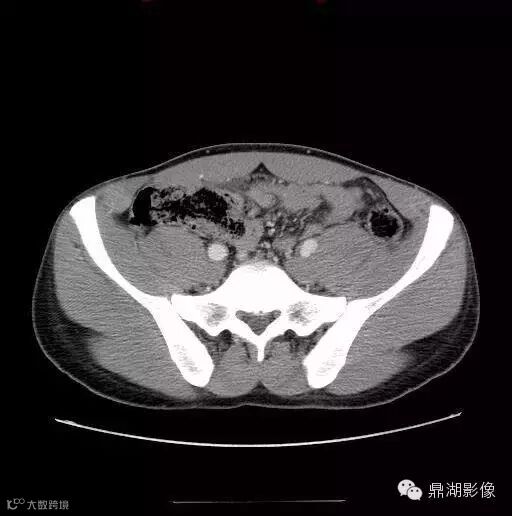

49岁男性,腹痛,恶心,呕吐,厌食。盆腔右侧可见圆形液体积聚(箭),内见钙化的肠石,邻近脂肪炎性改变。